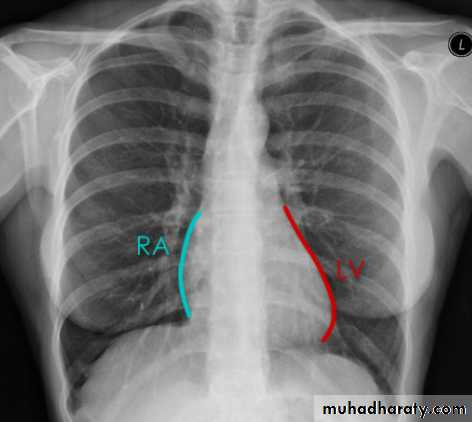

Cardiac borders in AP view

14.cardiac border in AP view